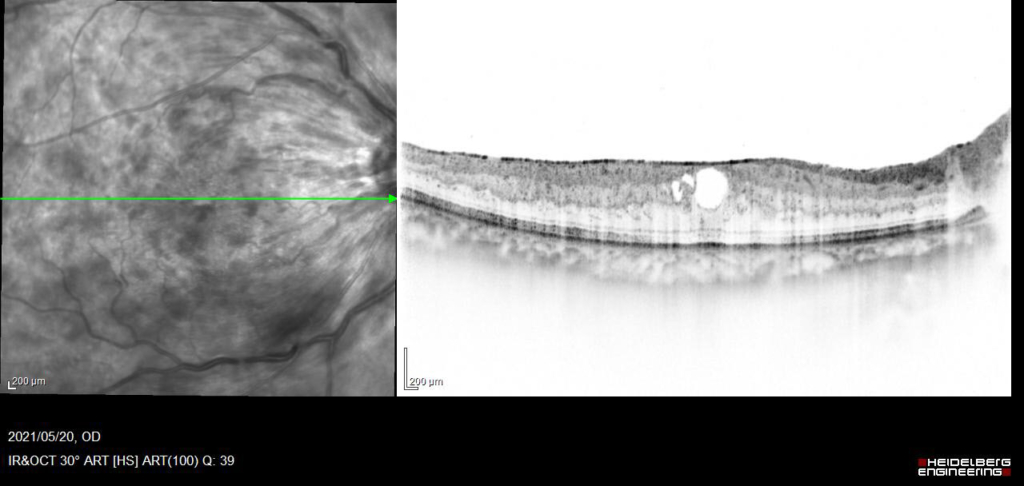

抗VGEF(ラニビズマブ)の硝子体注射2日後。

約4か月 抗VGEF(ラニビズマブ)の硝子体注射4回施行後、黄斑浮腫は注射直後に一時的に改善するが、4wで黄斑浮腫は著明に再発する。